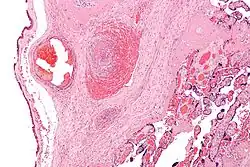

Одна из самых тяжёлых форм ДЦП, являющаяся следствием аномалий развития головного мозга, внутриутробных инфекций и перинатальной гипоксии с диффузным повреждением полушарий головного мозга. У недоношенных детей основной причиной при перинатальной гипоксии является селективный некроз нейронов и перивентрикулярная лейкомаляция; у доношенных — селективный или диффузный некроз нейронов и парасагиттальное поражение мозга при внутриутробной хронической гипоксии. Клинически диагностируется спастическая квадриплегия (квадрипарез; более подходящий термин[9], по сравнению с тетраплегией, так как заметные нарушения выявляются примерно одинаково во всех четырёх конечностях), псевдобульбарный синдром, нарушения зрения, когнитивные и речевые нарушения. У 50 % детей наблюдаются эпилептические приступы. Для данной формы характерно раннее формирование контрактур, деформаций туловища и конечностей. Почти в половине случаев двигательные расстройства сопровождаются патологией черепных нервов: косоглазием, атрофией зрительных нервов, нарушениями слуха, псевдобульбарными расстройствами. Довольно часто у детей отмечают микроцефалию, которая, разумеется, носит вторичный характер. Тяжёлый двигательный дефект рук и отсутствие мотивации исключают самообслуживание и простую трудовую деятельность.